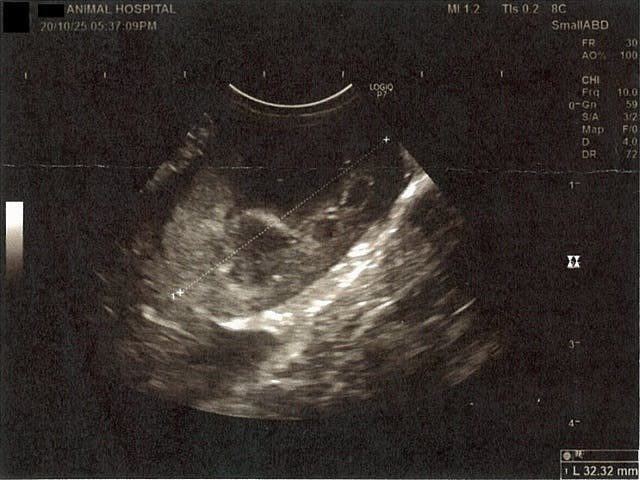

《心臓周りの胸部以外の全ての腹部で腹水がみられるとの診断です》

右腎臓周りに腹水が確認できるエコー写真

左腎臓周りに腹水が確認できるエコー写真